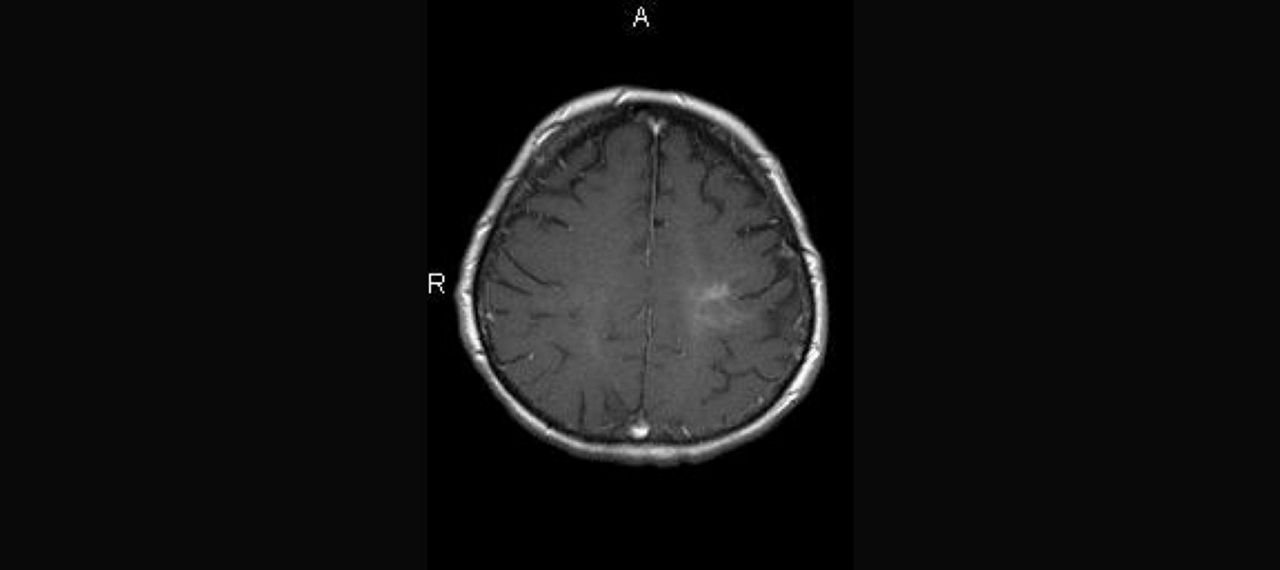

Abb.4: T1 + KM

Herd im cervikalen Myelon: kurzstreckig, ungefähr 1 cm groß

AUFLÖSUNG FALL 2

Diagnose: MS

AQP4-IgG: negativ

MOG-IgG: negativ

Conclusio: Auch bei MS kommen protrahierte Schübe und fehlendes Ansprechen auf Steroide vor